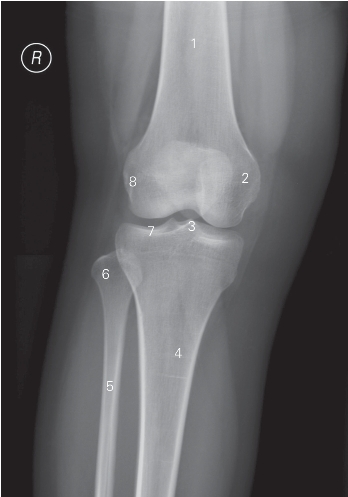

图7-6 膝关节正位DR平片

1 股骨 femur 2 股骨内侧髁 medial condyle of femur

3 髁间隆突 intercondylar eminence

4 胫骨 tibia 5 腓骨 fibular

6 腓骨头 fibular head 7 胫骨平台 tibial plateau

8 股骨外侧髁 lateral condyle of femur